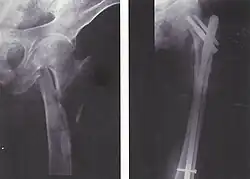

| Fratura da diáfise do fêmur com deslocamento e fragmentos. | |

Para fraturas da diáfise, a redução e haste intramedular são recomendados atualmente. O osso é realinhado, e em seguida uma haste de metal é fixada atravessando a medula óssea. A haste é estabilizada com pregos em cada extremidade. Este método oferece menos exposição, 98% de consolidação, menores taxas de infecção (1%-2%) e menos cicatrizes.[13]